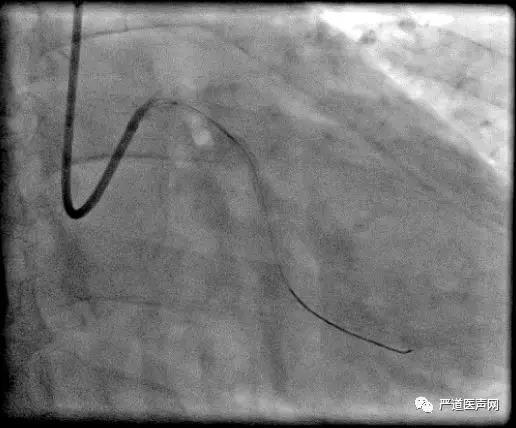

来自郴州市第一人民医院心血管病医院的王仲华主任为大家带来了一例右冠开口支架内CTO的精彩汇报。患者为55岁男性,2016年12月因“急性广泛前壁心肌梗死”于前降支近中段植入支架2枚,2017年2月在右冠近中段植入支架2枚。行双侧造影示:LAD支架畅通,与RCA形成侧支循环,RCA开口闭塞。由于RCA入口位置不定,指引导管无法判断是否到达入口,无法定位原支架的位置,而LAD有侧支循环,决定选择逆向途径。

手术策略为正向微导管等待逆向微导管及导丝。术中逆向入Sion导丝,Corsair 150mm微导管跟进困难,故更换Finecross 150mm微导管后顺利通过,逆向导丝升级入前向指引导管,但逆向微导管跟进困难,遂正向指引导管再入Corsair150mm微导管Rendexous成功。

前向Corsair微导管无法通过RCA C1段。原因可能为前向Guiding支持不足、支架内闭塞组织坚韧、原有病变钙化+支架膨胀不全、导丝行走于支架外等。遂后退逆向导丝、微导管,前向通过Sion导丝,但前向Corsair微导管仍然无法通过,退出,使用1.2mm球囊后扩张,最终植入两枚Excel(爱克塞尔)支架。